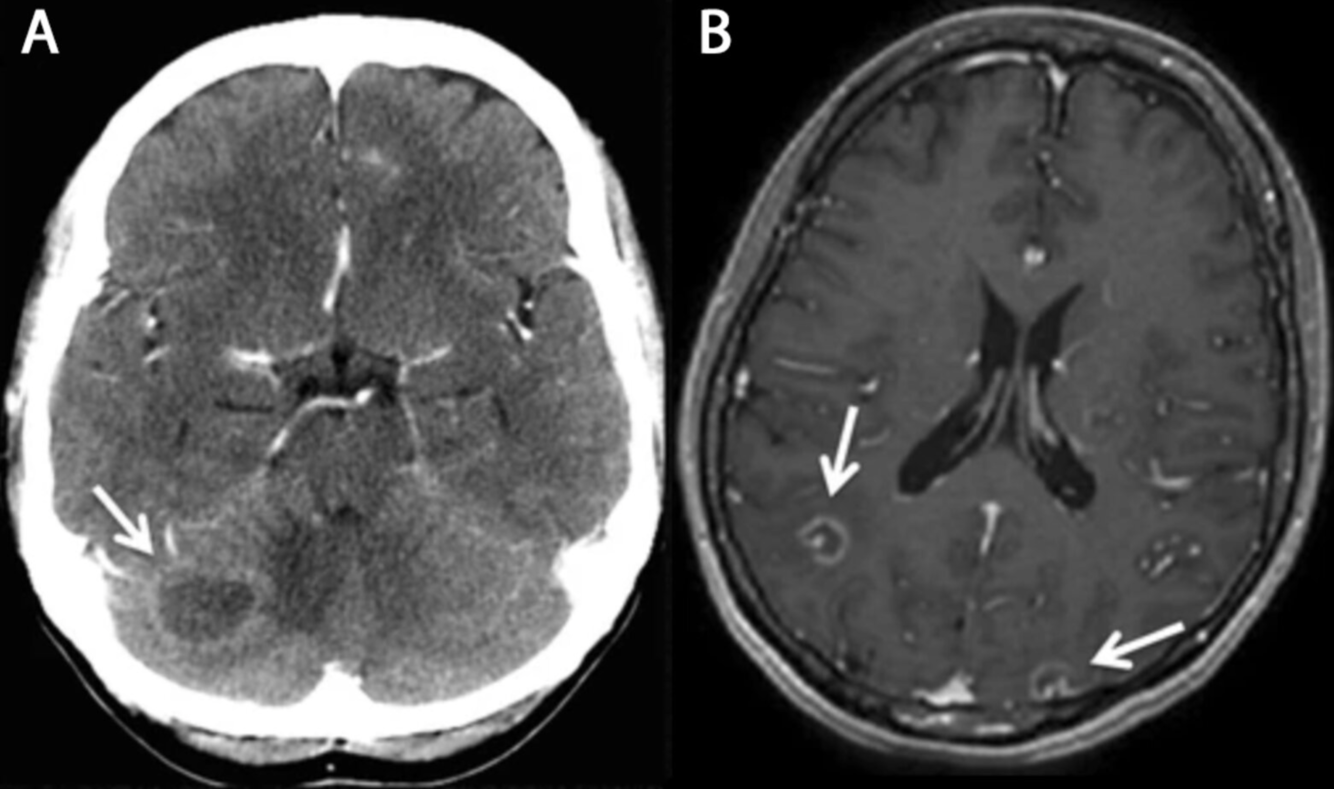

Toxoplasmose cérébrale